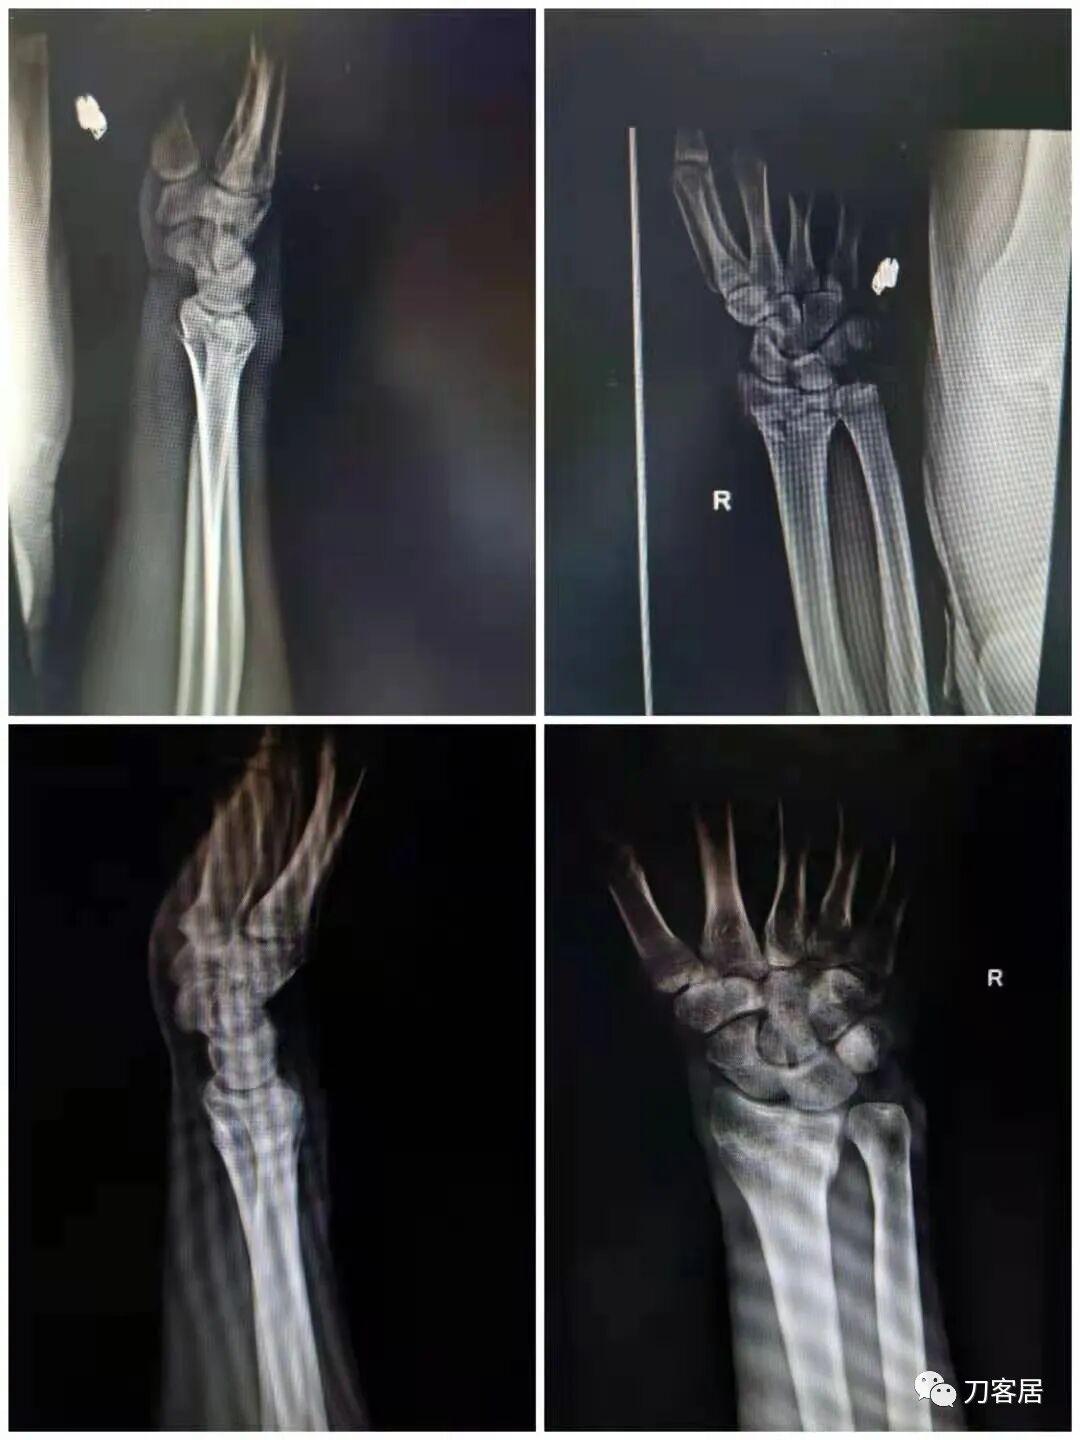

2021年7月22日晚,上海美华医院儿童骨科的师东良医生,给我提供了一例他处理的严重移位尺桡骨双骨折病例,经过手法复位,石膏外固定治愈。这个病例,其他医院建议要做手术。实际上,这样的病例,在现实中有太多太多,因为手法复位,石膏外固定治疗骨折,这是骨科医生的基本功。

下面为师东良医生提供的病例:

超声引导下闭合手法复位石膏外固定治疗7岁患儿尺桡骨远端移位双骨折。

男,7岁,左前臂远端桡尺骨双骨折,术前X光片见图1,行超声引导下闭合复位石膏外固定术,康复训练,6周拆石膏,随访2.5月的效果。术后2.5X光片见图23。功能上仅前臂旋后较健侧减小15°,继续加强康复训练中。家长满意,评价见图4

1. 超声引导下闭合复位石膏外固定术左尺桡骨双骨折

2. 超声引导下闭合复位石膏外固定术后2.5月左前臂正位X光片

3. 超声引导下闭合复位石膏外固定术后2.5月左前臂侧位X光片